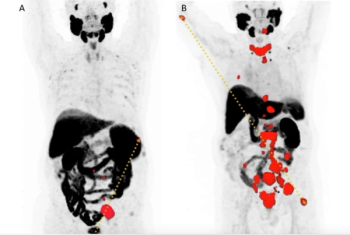

Doubling of total tumor volume on PSMA PET/CT is 41 percent more likely to reduce overall survival in patients with metastatic castration-resistant prostate cancer (mCRPC), according to new research.

In patients with high-risk, hormone sensitive prostate cancer who had no evidence of metastasis on conventional imaging, PSMA PET revealed polymetastatic disease in 24 percent of patients and M1 disease staging in 46 percent of patients.